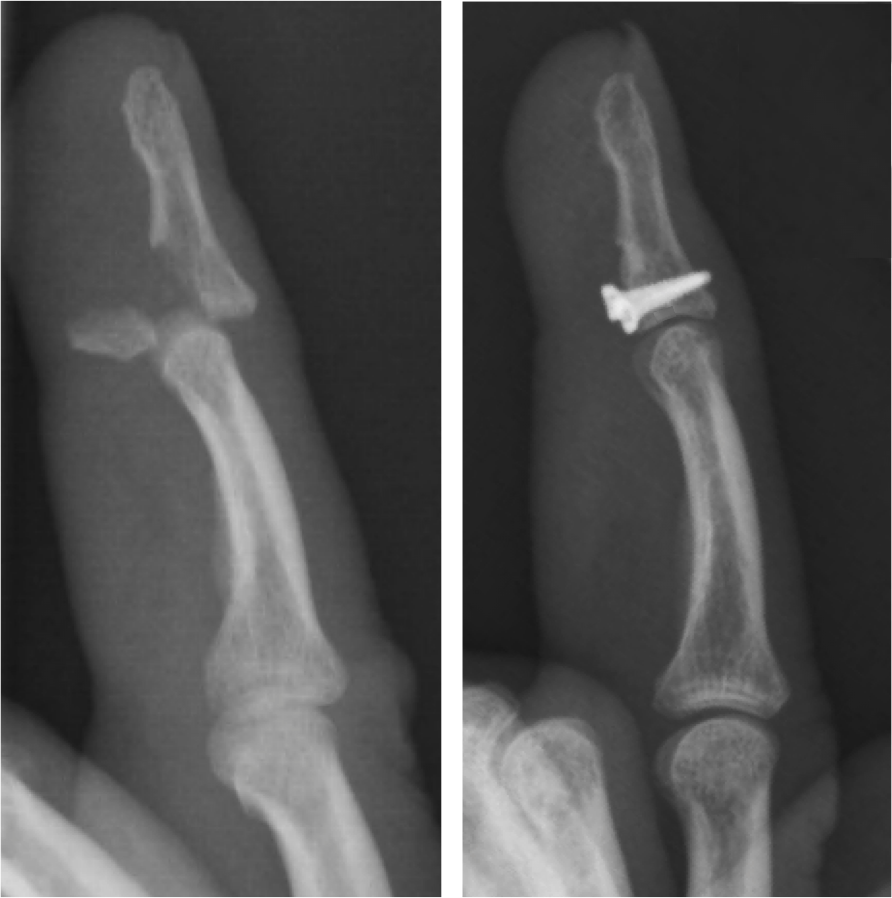

Fracture of the proximal phalanx bone of the ring finger. Spiral, oblique fractures such as this one tend to cause rotational deformities of the finger. In the x-ray on the left, the ring finger can be seen overlapping the pinkie finger. The abnormal positioning will adversely affect function of the finger if it is left to heal in this bent and rotated position. An outpatient procedure can improve the alignment and allow the bone to heal in a normal position. As shown above, the fracture is aligned, and temporary pins are placed through the skin (no incision) to hold the two fractured pieces together. The pins are removed 2-3 weeks later in the office, and motion is started. Strengthening and more vigorous activities are resumed once the fracture has healed (~6 weeks).